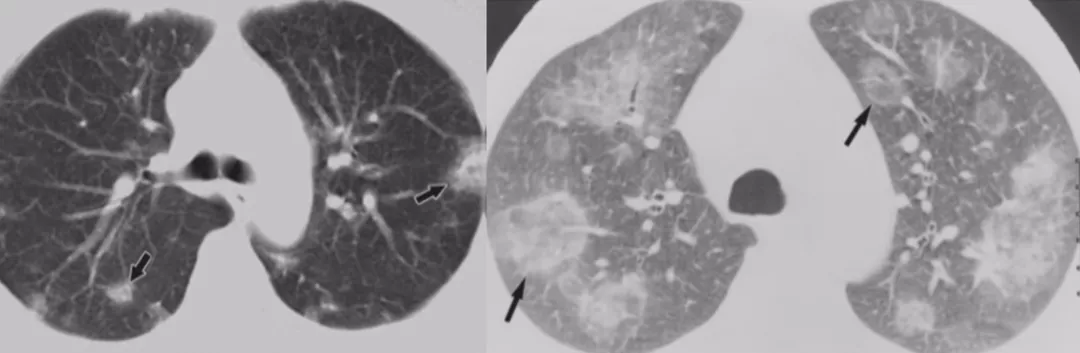

在临床上经常手术切除后发现是AAH,关于AAH的病人是否需要手术还存在很大的争议,有的认为不需要手术,观察就可以。那么我们在术前怎么评判是否为AAH?其实具有一定特征。一般来说,多位于肺外周,多<5mm,圆形或类圆形,边界清楚,多发更常见,绝大部分是均匀的纯磨玻璃影,里边没有实性成分。组织学检查AAH呈轻度到中度非典型立方柱状上皮细胞沿肺泡和呼吸性细支气管上皮增殖,无浸润,这样在临床上诊断AAH应该没有问题。但是,如下图所示,这个病人是多灶性病变,现在多灶性结节有所增多,会给临床的处理上带来一定压力。

原位癌(AIS)

接下来再发展就是原位癌。一般来说,多位于肺外周,多为单发,病灶比AAH更大,形状可为圆形、类圆形或不规则,边界清楚,可为纯磨玻璃影。现在计算机可以测量CT值,我们应该定量分析,观察CT值,不透明程度较AAH高。组织学呈纯粹的贴壁生长,无基质、血管或胸膜浸润。一旦遇到密度稍微高一点的磨玻璃结节,要谨慎,它很可能已经是原位癌,此时手术仍然是非常理想的效果。